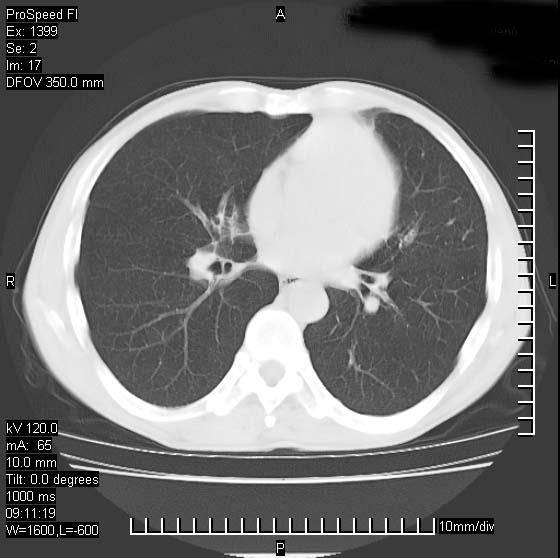

以下是引用卜一在2007-1-19 9:55:00的发言:[br]左肺沿胸膜下巨大肿块影,边缘呈分叶征,纵隔内见肿大淋巴结,右肺内另见一不规则结节影 .考虑:左肺周围性肺癌伴纵隔 右肺内转移.

以下是引用rgsyyf在2007-1-19 11:05:00的发言:[br]左肺上叶见形态不规则巨大软组织肿块影,边缘呈分叶征,纵隔内隆突下见肿大淋巴结,右肺内另见一不规则结节影 .考虑:左肺周围性肺癌伴纵隔即右肺内转移.